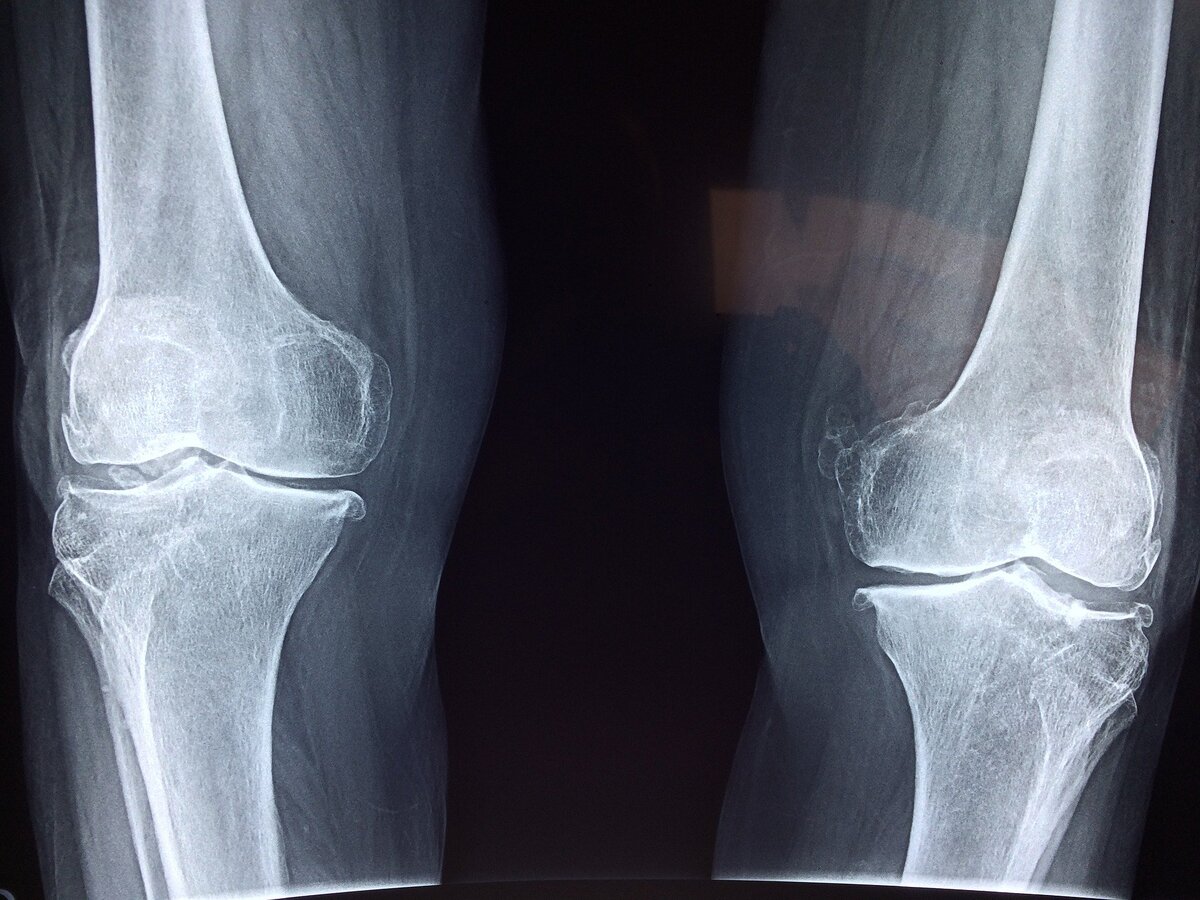

Суставы — подвижные соединения костей скелета, которые участвуют в перемещении отдельных костных рычагов относительно друг друга, в передвижении тела в пространстве и сохранении его положения. Травмы суставов либо не лечатся вообще, либо лечение будет стоить огромных денег и сил. Теперь вспомните своих пожилых родственников, наверняка, почти у каждого из них есть проблемы с суставами (к слову о распространенности). Очевидно, что к суставам нужно относиться с особой внимательностью.

Избыточный вес неизбежно вызывает дегенеративные изменения в коленных и тазобедренных суставах. Иногда человеку с ожирением "везет" и он умирает до того, как сотрется суставной хрящ и он начнет чувствовать боли в суставах, иногда - нет. Старайтесь поддерживать свой вес в норме, информации по этому вопросу достаточно, ничего сложного в этом нет.